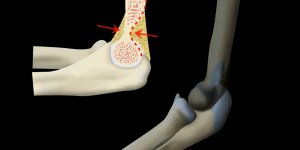

Supracondylar Fracture | X-ray

Published on May 4, 2020

Simple x-ray interpretation of a supracondylar fracture and its mechanism of injury.